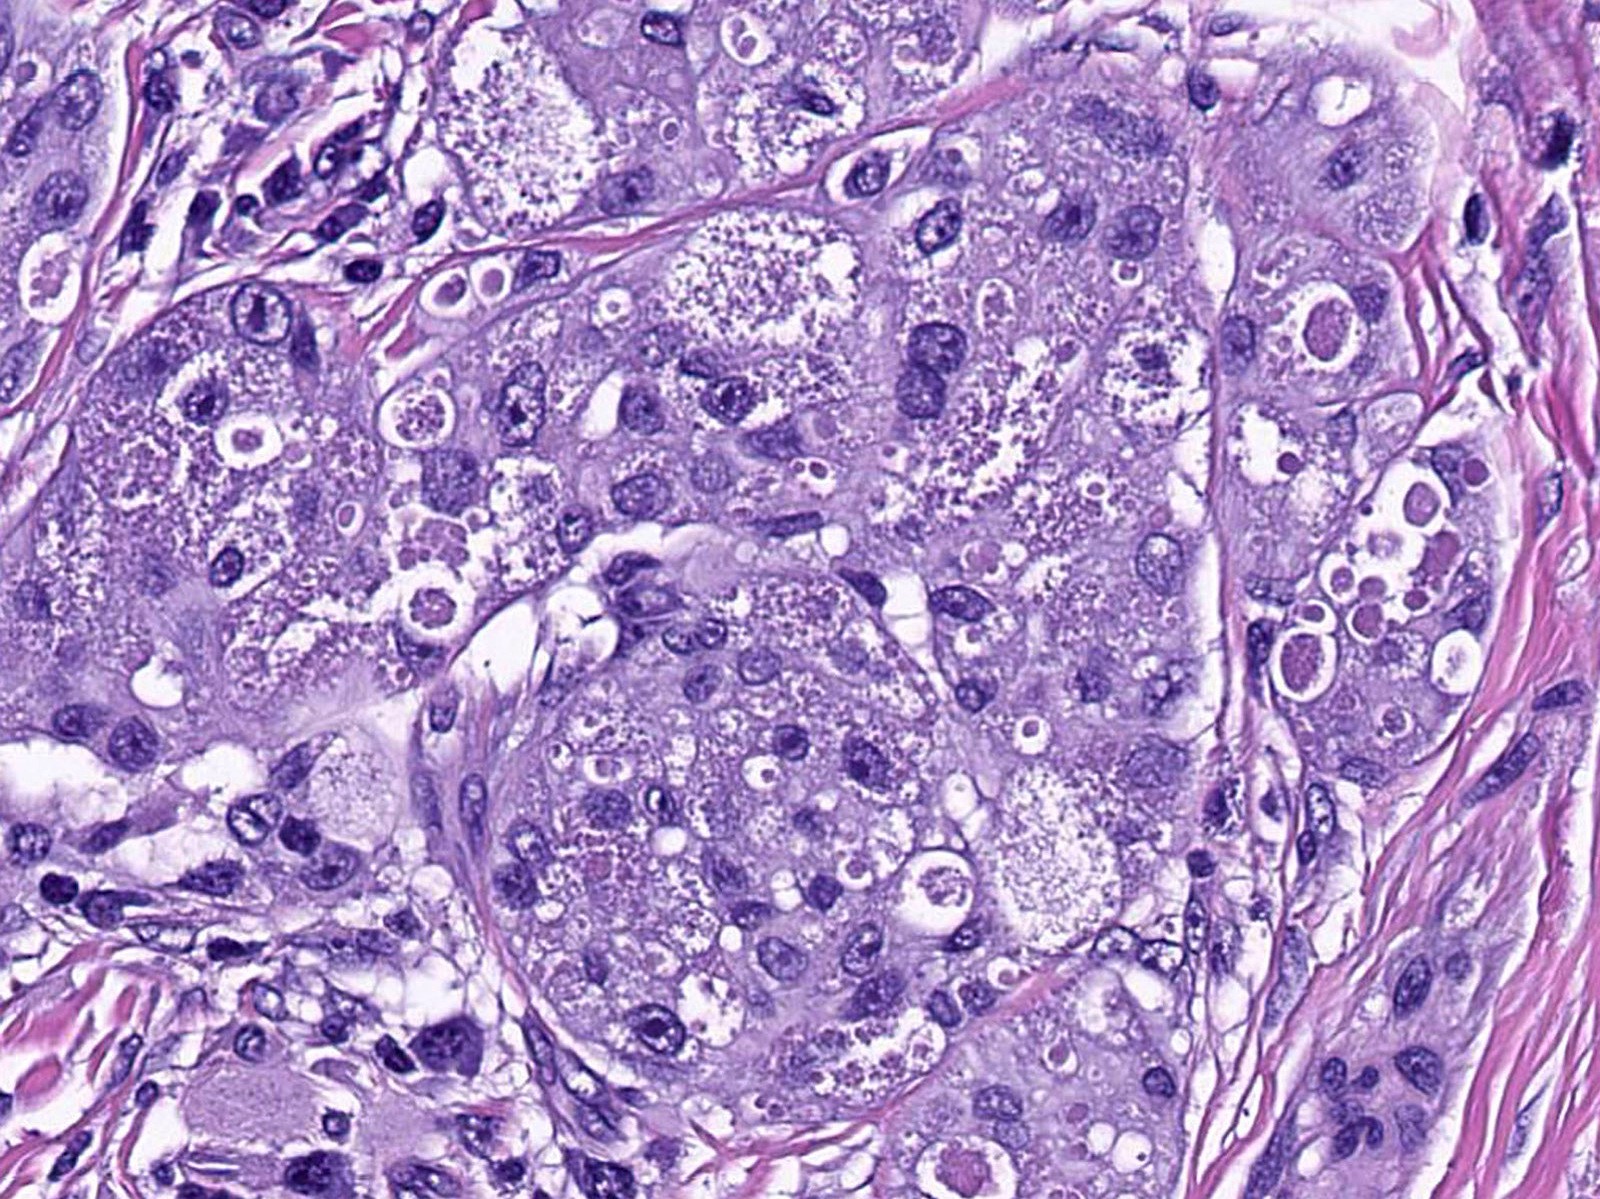

Microscopic (histologic) description

- Large polygonal cells with abundant eosinophilic granular cytoplasm and small, central nuclei

- Lysosomal macroinclusions (pustulo-ovoid bodies of Milian) are usually present (J Cutan Pathol 2007;34:405)

- Nonneural granular cell tumors (S100-) can exhibit nucleomegaly, pleomorphism and variable mitotic activity (Am J Surg Pathol 1991;15:48, Histopathology 2005;47:179)

Microscopic (histologic) images

Contributed by Jarish Cohen, M.D., Ph.D.